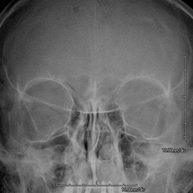

- Skull X-ray

This technique uses X-ray rendered imaging for examining the skull. Indicated for: trauma, premature cranial suture closure.

- Paranasal Sinuses X-ray

This technique uses X-ray rendered imaging for examining the paranasal sinuses. Indicated for: difficulty breathing through the nose, chronic cough, headache, mucus.